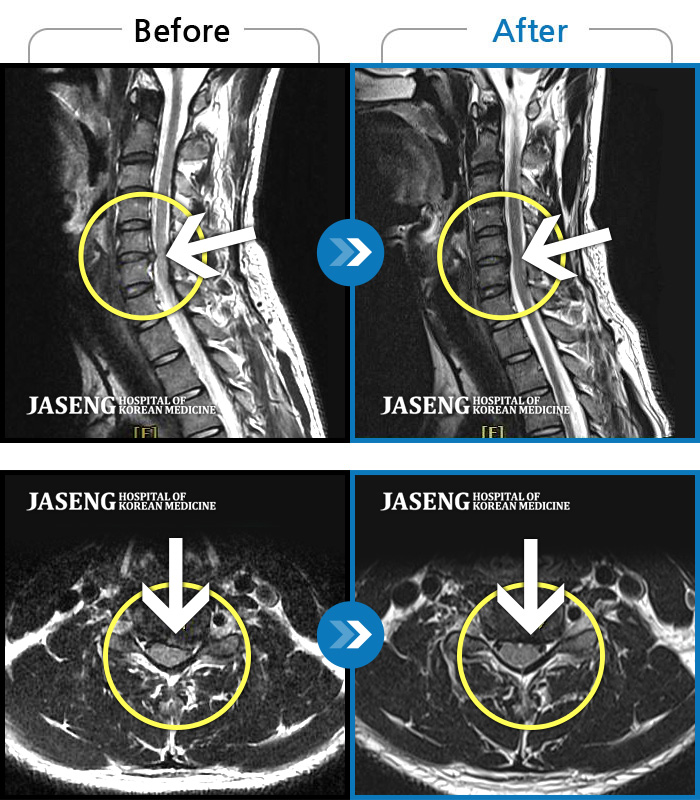

자생 비수술 한방통합치료 후

터진디스크가 흡수된 모습

Before

After

비수술 치료만으로

터진 디스크 흡수

양측 목, 어깨, 팔에 찌릿한 통증으로 일상생활에 지장이 있었습니다.

2020.08.14 ~ 2025.07.02